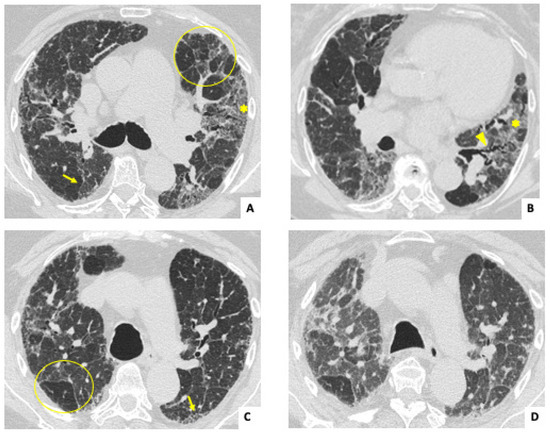

3.2. Radiological and Lung Function Findings

| Radiological features in HRCT | ||||

| Nodules, n (%) | 2 (8.7) | 2 (15.3) | 0 (0) | 0.092 |

| Lung consolidation, n (%) | 8 (34.8) | 2 (15.3) | 6 (60) | 0.039 |

| Ground glass opacities, n (%) | 17 (73.9) | 9 (69.2) | 8 (80) | 0.66 |

| Traction bronchiectasis, n (%) | 19 (82.6) | 13 (100) | 6 (60) | 0.024 |

| Reticulation, n (%) | 15 (65.2) | 10 (76.9) | 5 (50) | 0.179 |

| Honeycomb, n (%) | 8 (34.8) | 5 (38.4) | 3 (30) | 0.673 |

| Radiological pattern in HRCT | ||||

| UIP, n (%) | 12 (52.2) | 9 (69.2) | 3 (30) | 0.161 |

| NSIP, n (%) | 6 (26) | 1 (7.7) | 5 (50) | 0.022 |

| Fibrotic NSIP, n (%) | 5 (21.7) | 4 (30.7) | 1 (10) | 0.09 |

| OP, n (%) | 5 (21.7) | 3 (23) | 2 (20) | 0.673 |

| Radiological progression in HRCT, n (%) | 15 (65.2) | 9 (69.2) | 6 (60) | 0.685 |